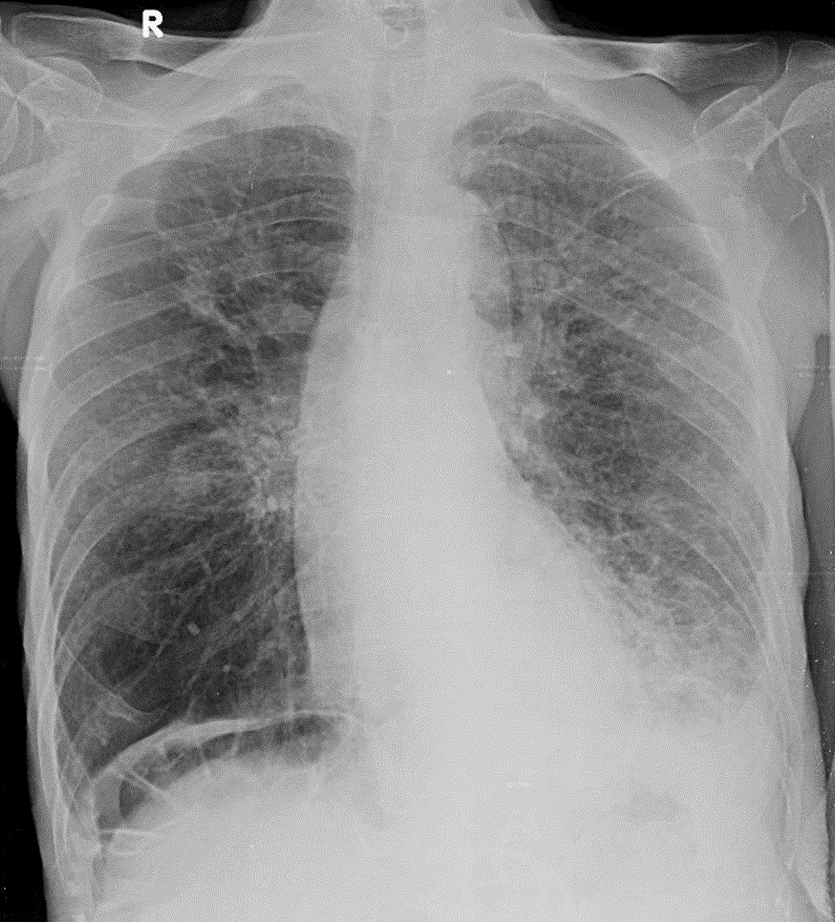

1-Xơ thùy trên phổi (P) 2-Thâm nhiễm thùy dưới phổi (T)=> Viêm phổi 3-Tràn dịch màng phổi (T) lượng ít 4-Bất thường hơi đại tràng góc gan nằm giữa vòm hoành và bờ trên gan (P)=> Hội chứng Chilaiditi